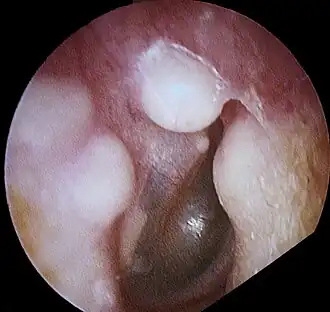

Диагноз остеомы ставят на основании клинико-рентгенологических данных. Дифференциальный диагноз между хроническим остеомиелитом и остеогенной саркомой легко установить на основании рентгенологической картины и течения заболевания.

Лечение остеом только хирургическое. Оно показано при клинической симптоматике или с косметической целью. Операция состоит в удалении опухоли с обязательной резекцией подлежащей пластинки здоровой кости. В случаях бессимптомного течения и небольших размеров опухоли считают целесообразным лишь динамическое наблюдение.

Во время операции врач разрезает ткани, а далее удаляет нарост и часть кожи или тканей вокруг по избежание рецидива.